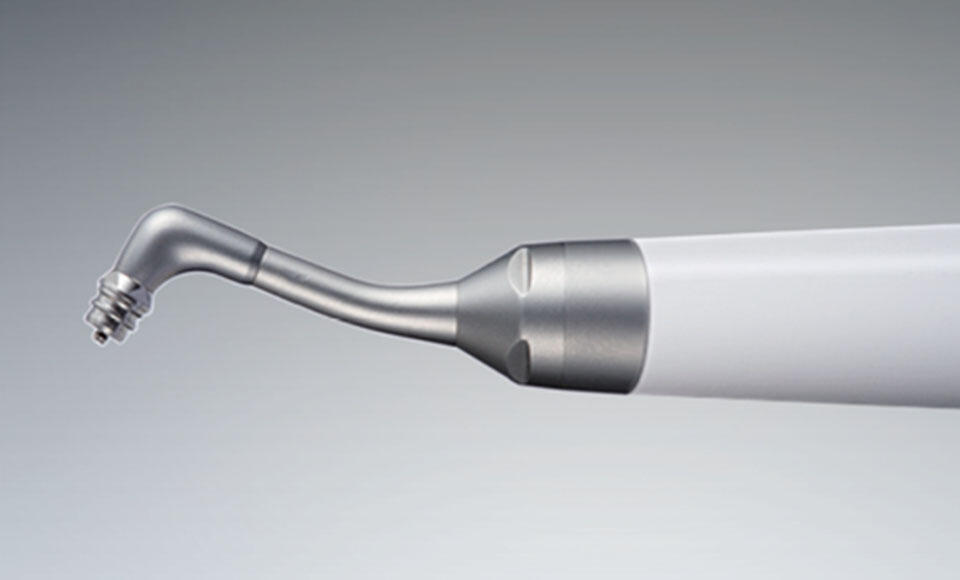

L’ultimo modello proposto dall’azienda NSK è il “VARIOS COMBI PRO”.

La Varios Combi Pro NSK permette al clinico di lavorare in maniera confortevole sfruttando le varie funzioni di trattamento ultrasonico ed air polishing per applicazioni sopragengivali e sottogengivali, garantendo un efficace controllo del biofilm ed un'accurata igiene professionale.